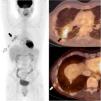

18FDG-PET-CT (fig. 1) showed confluent hypermetabolic nodules in the right lower lobe (RLL) consistent with reactivation of pulmonary sarcoidosis (black arrows). Besides, two small hypermetabolic subcutaneous nodules were revealed in the right thoracic wall. After carefully reviewing the medical record and the previous CT images, we arrived at the diagnosis of scar sarcoidosis at the scar of a video-assisted thoracoscopic biopsy of the RLL performed 10 years before, during the initial diagnostic work-up (white arrows). Treatment with infliximab was initiated and both the pulmonary and the cutaneous lesions resolved completely, thus confirming the diagnosis.Cutaneous sarcoidosis has many forms and affects 25% of patients with sarcoidosis. Scar sarcoidosis, an uncommon form of cutaneous sarcoidosis, represents less than 3% of the cases of skin involvement1. It consists in the development of sarcoid granulomas on previous scar tissue, and it should not be mistaken with keloids.

18FDG -PET-CT is an emerging tool for the staging and response assessment of sarcoidosis2. In this case, the high sensibility of 18FDG-PET was key to detect the granulomas, whereas the spatial and contrast resolution of the CT allowed the precise characterization of their location and nature.